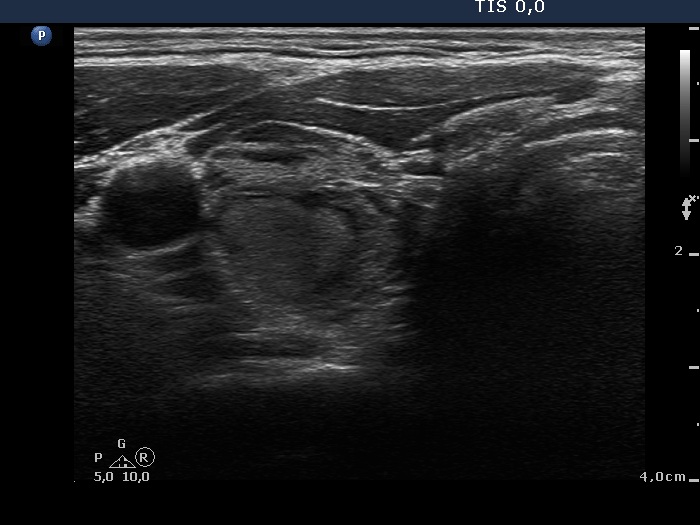

Discrete lesion or nodule in Hashimoto's thyroiditis - case 30 (812) (ultrasonographic picture 2)

Lower part of the right lobe, transverse view. There is a minimally hypoechogenic discrete lesion in the dorsal part of the right lobe.